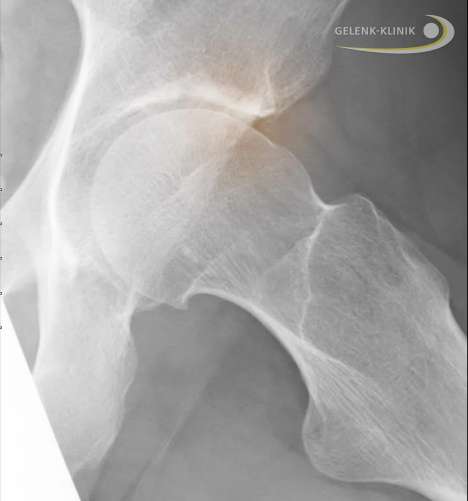

Hüftgelenk mit Cam-Impingement. Das Cam- oder Nockenwellen-Impingement ist eine knöcherne Erhöhung am Oberschenkelkopf, die an die Hüftpfanne (Acetabulum) anschlägt (rot eingezeichnet). © Gelenk-Klinik.de

Das Hüftimpingement (femoroacetabuläres Impingement oder kurz FAI) wurde erst vor einigen Jahren als wichtigste Ursache der Hüftarthrose erkannt. Wir haben in unserer Klinik ebenfalls festgestellt, dass viele Patienten, die früh an Hüftarthrose erkrankten, keine kugelförmigen Oberschenkelköpfe hatten. Diese Formveränderung führt zu bewegungsabhängigen Hüftschmerzen. Der Hüftspezialist kann das Hüftimpingement sehr gut klinisch oder durch Röntgenbilder diagnostizieren. Die Früherkennung des Hüftimpingements ist wichtig, weil es einen gelenkerhaltenden operativen Eingriff erlaubt.

Der Orthopäde kann die Form des Oberschenkelkopfes operativ wiederherstellen, bevor das dauernde knöcherne Anschlagen (engl. "to impinge") bei bestimmten Bewegungen zur Hüftarthrose führt. Das macht die Hüftarthroskopie bei Hüftimpingement zu einer wichtigen, das Hüftgelenk erhaltenden Operation.